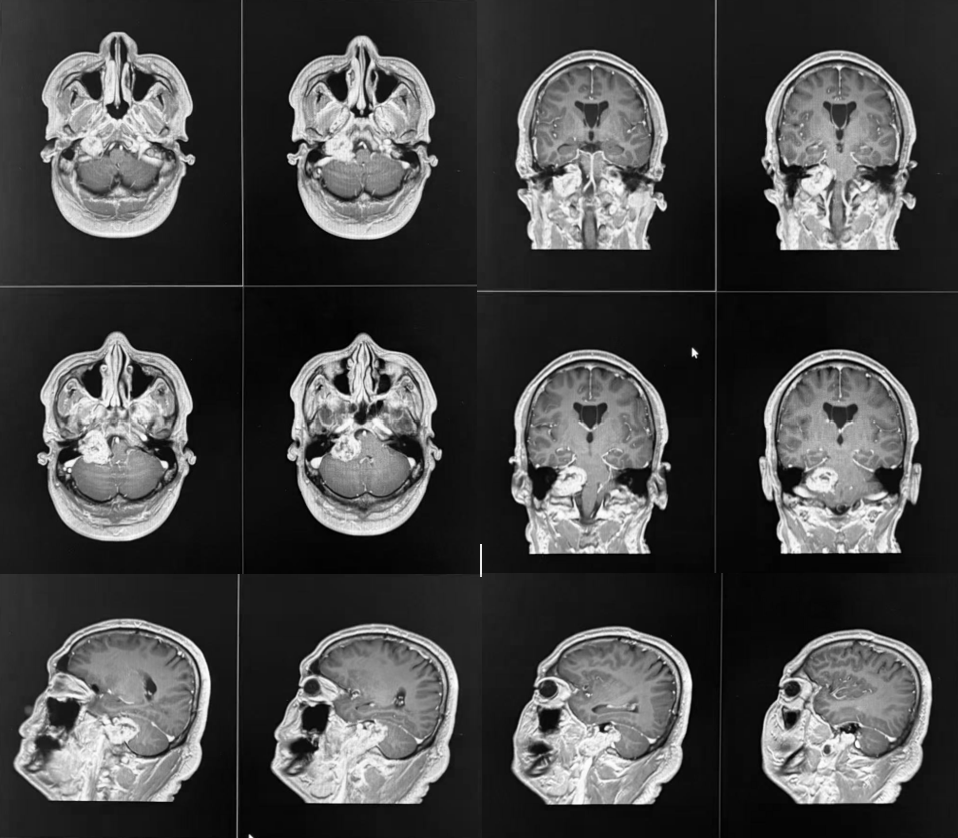

术前MRI检查

34岁的高先生(化名)近半年来右耳听力进行性下降,近一个月症状加重,并陆续出现右侧面部麻木、口角歪斜、声音嘶哑、言语及吞咽困难(饮水呛咳)等表现。此前多地检查未明确病因,经多方打听,他慕名来到交大一附院榆林医院就诊。神经外科二病区纪文军主任医师接诊后,结合患者症状及影像学检查,确诊其为桥小脑角-颈静脉孔区囊实性占位病变。肿瘤体积较大,已压迫脑干及后组颅神经,若不及时手术,可能进一步危及生命并加重神经功能障碍,手术指征明确。